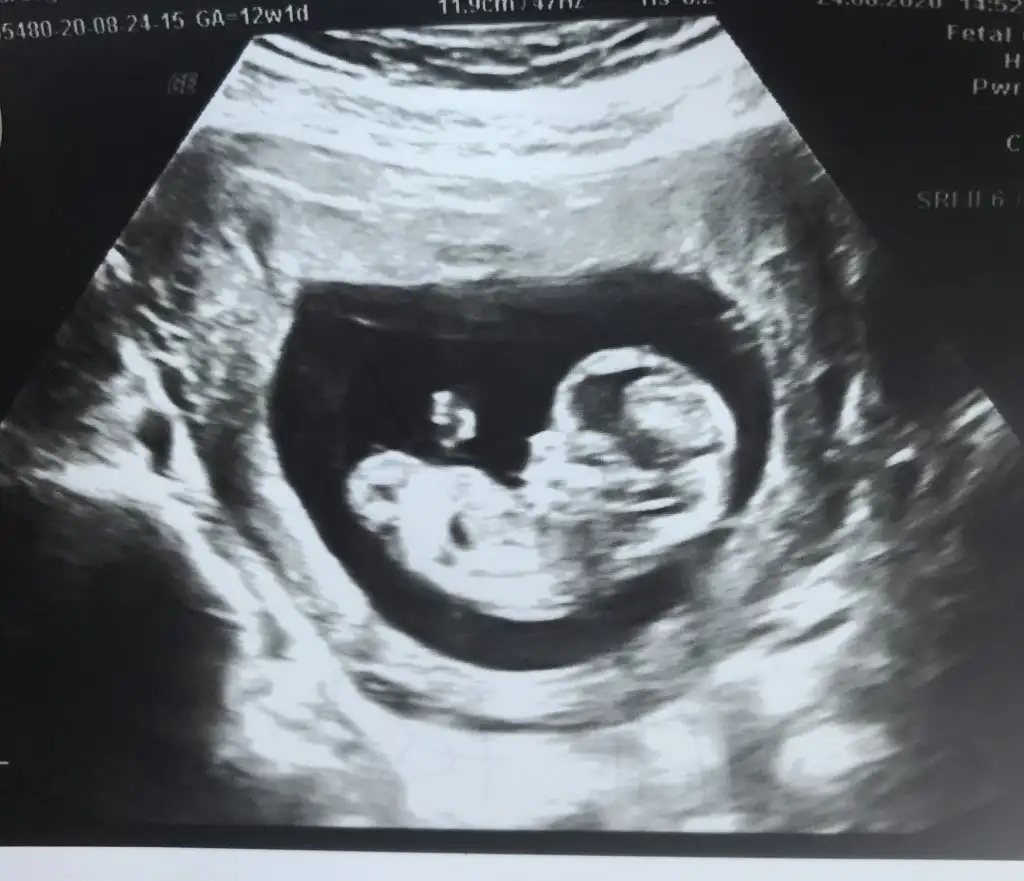

Erkek bebişMerhaba, 12. haftadan ultrason görüntülerimiz. Yorum yaparsanız çok sevinirim.Eki Görüntüle 2678844 Eki Görüntüle 2678845 Eki Görüntüle 2678846 Eki Görüntüle 2678844 Eki Görüntüle 2678845 Eki Görüntüle 2678846 Eki Görüntüle 2678844 Eki Görüntüle 2678845 Eki Görüntüle 2678846 Eki Görüntüle 2678846 Eki Görüntüle 2678844 Eki Görüntüle 2678845 Eki Görüntüle 2678846 Eki Görüntüle 2678844 Eki Görüntüle 2678845 Eki Görüntüle 2678846

Bana da öyle geldi bi de erkek olsa belli olurdu bu hafta dedi cogu kisi. Kız daha geç görünüyormuş bakalım ne cikacak iki hafta sonra yazarımKız gibi sanki